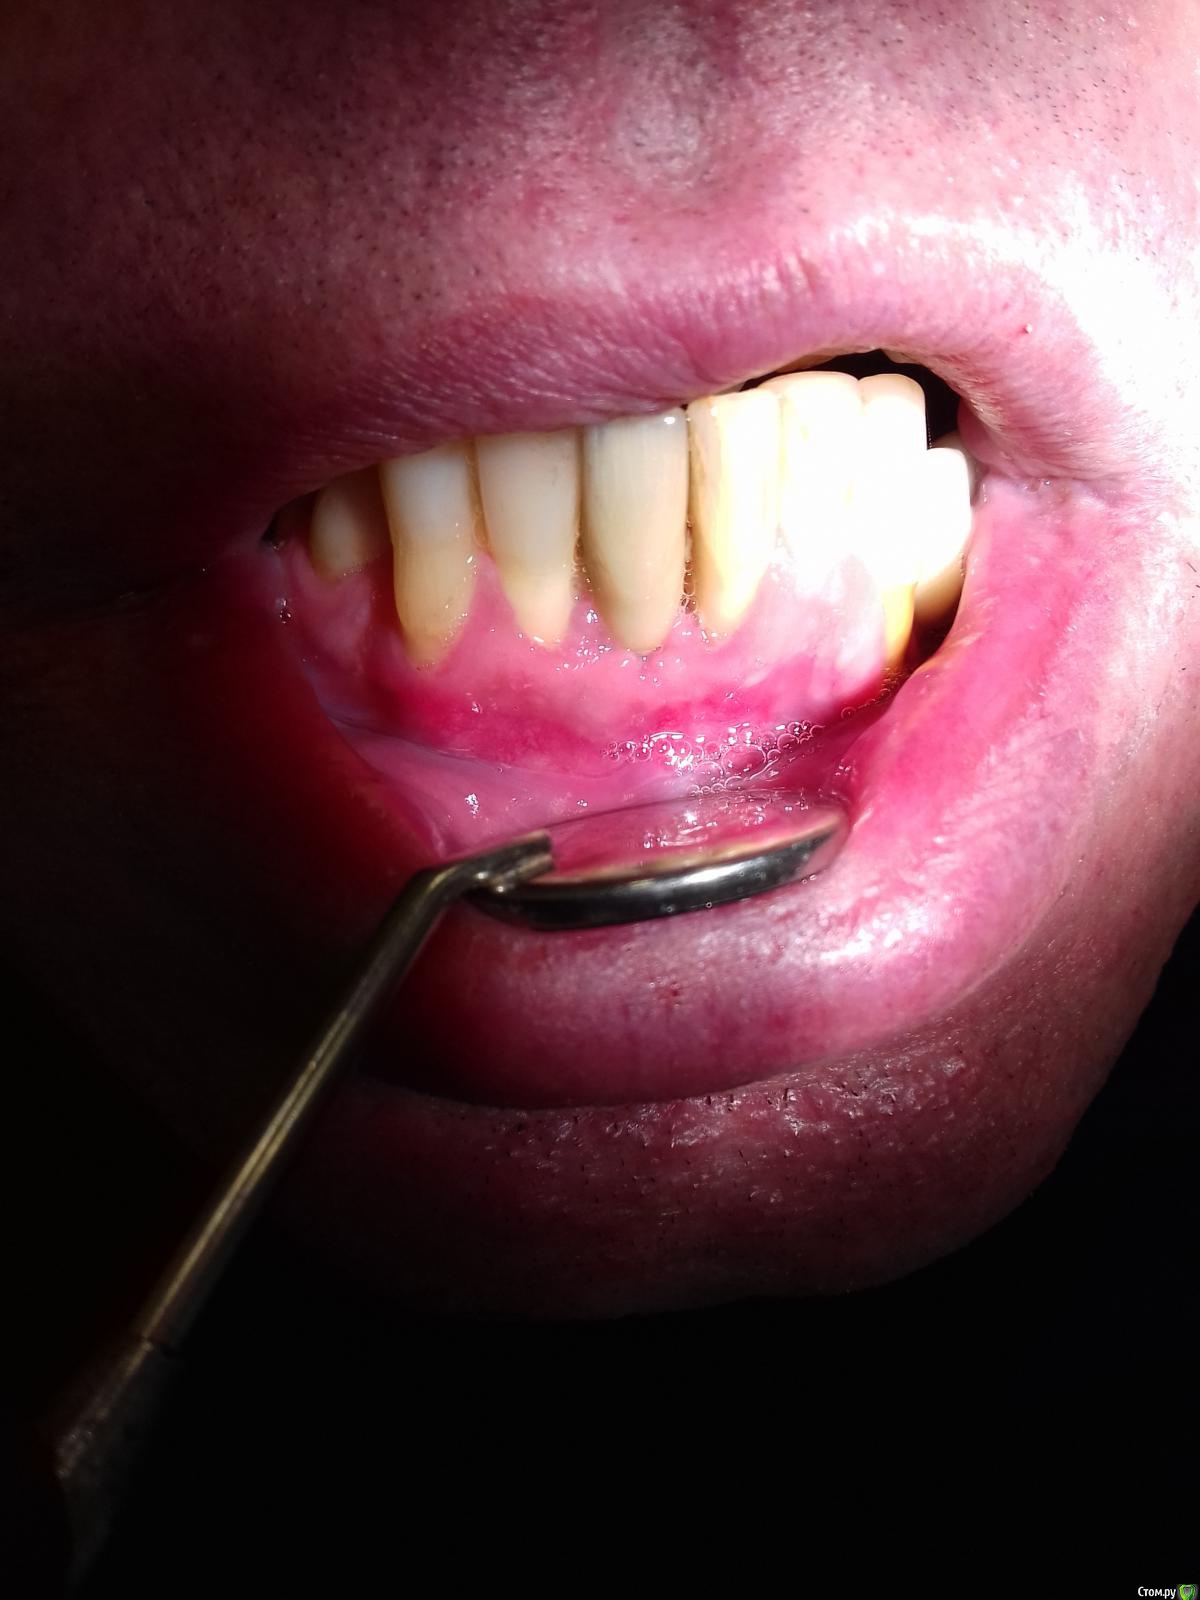

Jurai Опубликовано 25 декабря, 2016 Поделиться Опубликовано 25 декабря, 2016 *Предупреждение: фото на "мыльницу", не все этапы удались, но я работаю над этим) Вот пациент. Приятнейший, во всех отношениях, с негативным отношениям к мостовидным конструкциям. Полтора года лечил 41з по поводу периодонтита: толку не вышло. Удалил у широко известного многим стоматологам, особенно выпускам последних годов, доктора с ученой степенью. После удаления 4 месяца, по КТ область вполне достойно выглядит. Вот с чем пришел, обычное дело, все прилично: Раскрываю, а там между тонкими кортикалками мягко и упруго - резидуальная, фото нет. Открываю сильнее чем обычно, с расстройства не особо удачно. Кюретаж : Вид после, ушла вестибулярная кортикальная вместе с кистой: Сверлим 2,0, позиционердля рентген-контроля Имплантат ADIN UNP2,75Х11,5мм Ауто, джейсон коллагенфлис (что было под рукой) Швы. Контроль, перещелкивать не стали. В общем, понравился имплантат, для себя пометку кюретажить тщательнее, не надеяться, что организм все переварит. 1 9 Ссылка на комментарий